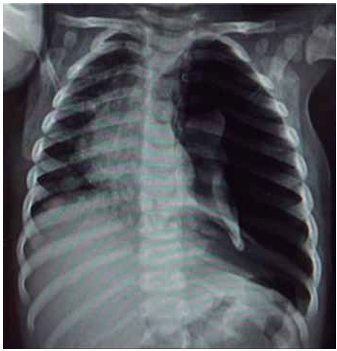

Lactente de 1 ano com diagnóstico de bronquiolite com sinais evidentes de desconforto respiratório. Apesar das medidas de suporte, ausência de melhora clínica e necessidade de intubação (IOT); logo após o procedimento, apresentou melhora da saturação de oxigênio e do padrão respiratório e foi acoplado à ventilação mecânica com parâmetros elevados. Aproximadamente 1 hora depois, iniciou com piora progressiva da saturação (queda sustentada até 78%), diminuição da ausculta pulmonar e da expansibilidade à esquerda, com respiração assincrônica. Averiguada posição da cânula, adequada e não obstruída. Exame físico com aparente piora hemodinâmica, FC = 174 bpm, PA = 64 x 32 (40) mmHg e pulsos finos. Realizada radiografia de tórax a seguir.

Enunciado 4584204-1

(Arquivo pessoal; imagem usada com autorização)

Considerando os dados apresentados, assinale a alternativa que descreve a melhor conduta para a condição atual do paciente.